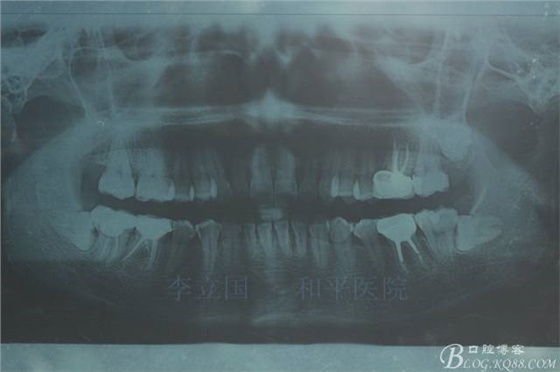

2.Damonclear排齊整平。

3.微種植支抗內(nèi)收上下前牙。

4.調(diào)整咬合關(guān)系。

治療要點(diǎn):

1.患者上前牙直立,面型前突,典型的嘴凸牙不吐,關(guān)鍵是前牙轉(zhuǎn)矩控制,建議使用高轉(zhuǎn)矩托槽。

2.磨牙關(guān)系一側(cè)完全遠(yuǎn)中,一側(cè)遠(yuǎn)中尖対尖,采用兩個(gè)上4,一個(gè)下1的拔牙模式。

3.上頜應(yīng)用支抗釘。表麻下在56牙槽間隔植入,注意因使用的為鈦合金釘,一直保持植入角度與骨面成60度角,不要垂直植入再改變角度。要求即刻加載,即刻加載力值2盎司。

4.使用長(zhǎng)牽引鉤,使?fàn)恳咏项M骨阻抗中心,防止上頜骨的順時(shí)針旋轉(zhuǎn)。

5.回收過程中,上下前牙輕搖椅,防止覆合加深。